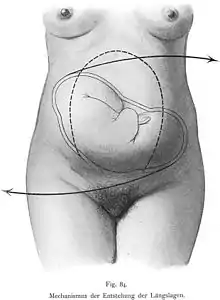

The fetal head may temporarily change shape (becoming more elongated or cone shaped) as it moves through the birth canal. This change in the shape of the fetal head is called molding and is much more prominent in women having their first vaginal delivery.[29]

Second stage: fetal expulsion

The expulsion stage begins when the cervix is fully dilated, and ends when the baby is born. As pressure on the cervix increases, a sensation of pelvic pressure is experienced, and, with it, an urge to begin pushing. At the beginning of the normal second stage, the head is fully engaged in the pelvis; the widest diameter of the head has passed below the level of the pelvic inlet. The fetal head then continues descent into the pelvis, below the pubic arch and out through the vaginal opening. This is assisted by the additional maternal efforts of pushing, or bearing down, similar to defecation. The appearance of the fetal head at the vaginal opening is termed crowning. At this point, the mother will feel an intense burning or stinging sensation.